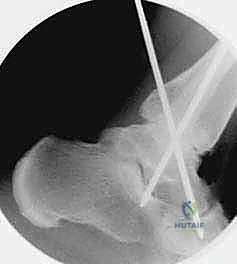

هو إحداث توازن مثالي بين الجراحة المفتوحة وجراحة المناظير. يقوم الأستاذ الدكتور محمد هطيف بإجراء الجراحة عبر شقين أو ثلاثة شقوق صغيرة جداً (لا تتجاوز 2-4 سم). من خلال هذه النوافذ الصغيرة، وباستخدام أدوات جراحية دقيقة ومخصصة، يتمكن من الرؤية المباشرة للمفصل، وإزالة الغضاريف التالفة بالكامل، وتجهيز العظام للدمج، ثم تثبيتها بالبراغي.

- التصوير المقطعي المحوسب (CT Scan): إجراء بالغ الأهمية قبل الجراحة. يوفر صوراً ثلاثية الأبعاد للعظام، مما يساعد الدكتور هطيف في تقييم جودة العظم بدقة، تحديد حجم التكيسات العظمية، والتخطيط الهندسي الدقيق لزوايا إدخال البراغي الجراحية.